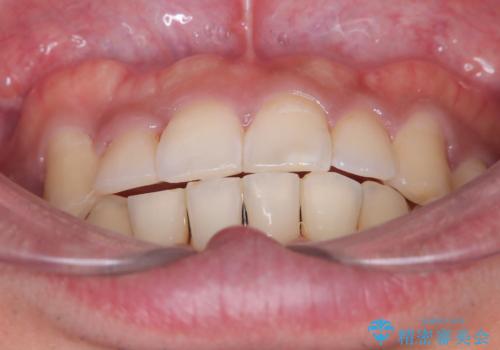

【ワイヤー矯正】八重歯と下の歯の凸凹を治したい

- 主訴:右上の八重歯と、下の歯の凸凹を治したい

上顎右側第一小臼歯と下顎右側第一小臼歯を抜歯しワイヤー矯正を行いました。

右側2級、左側1関係だったため、右側上下第一小臼歯を抜歯し、ワイヤー矯正を行いました。

期間:2年6カ月